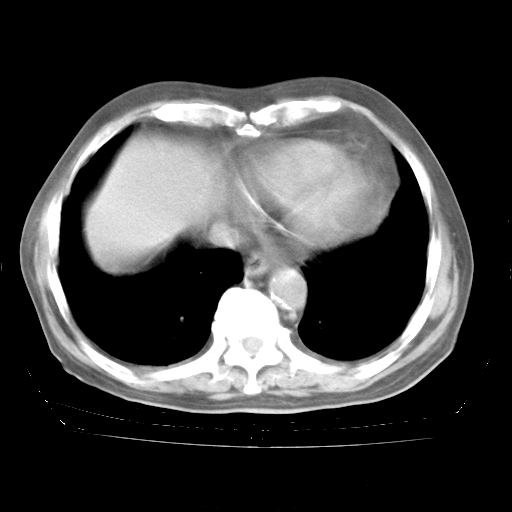

4月28日肺部CT——再次出现类似去年5月9日——透光度降低,“间质性”改变。